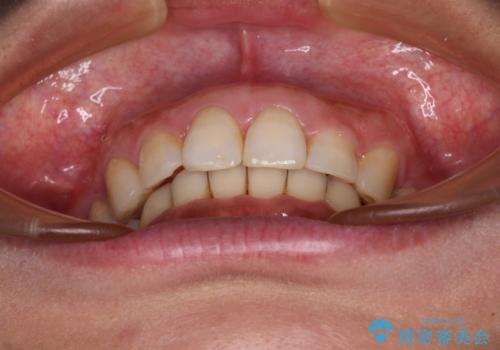

- 以前行った抜歯矯正が後戻りし、開いてしまったスペースが気になるとのことで来院された患者様です。

インビザラインを用いて開いてしまったスペースと前歯のデコボコを改善することとしました。

矯正治療後には気になっていた銀歯をセラミッククラウンやセラミックインレーにて治療することとしました。

上顎前歯を左右対称となるように歯列を整えたいとのことでしたが、すり減って形態が大きく異なっていたため、できる範囲での仕上がりとなりました。